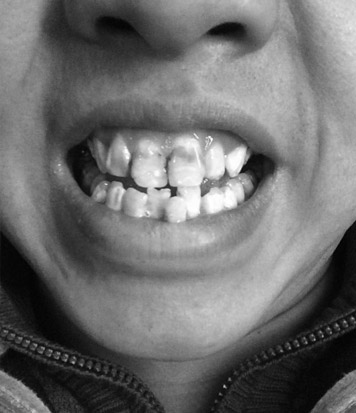

美莱Invisalign隐适美医生会进行拍照、X 光检查和数字扫描或取模,以便为您制定治疗方案。

医生进行检查

制定治疗方案